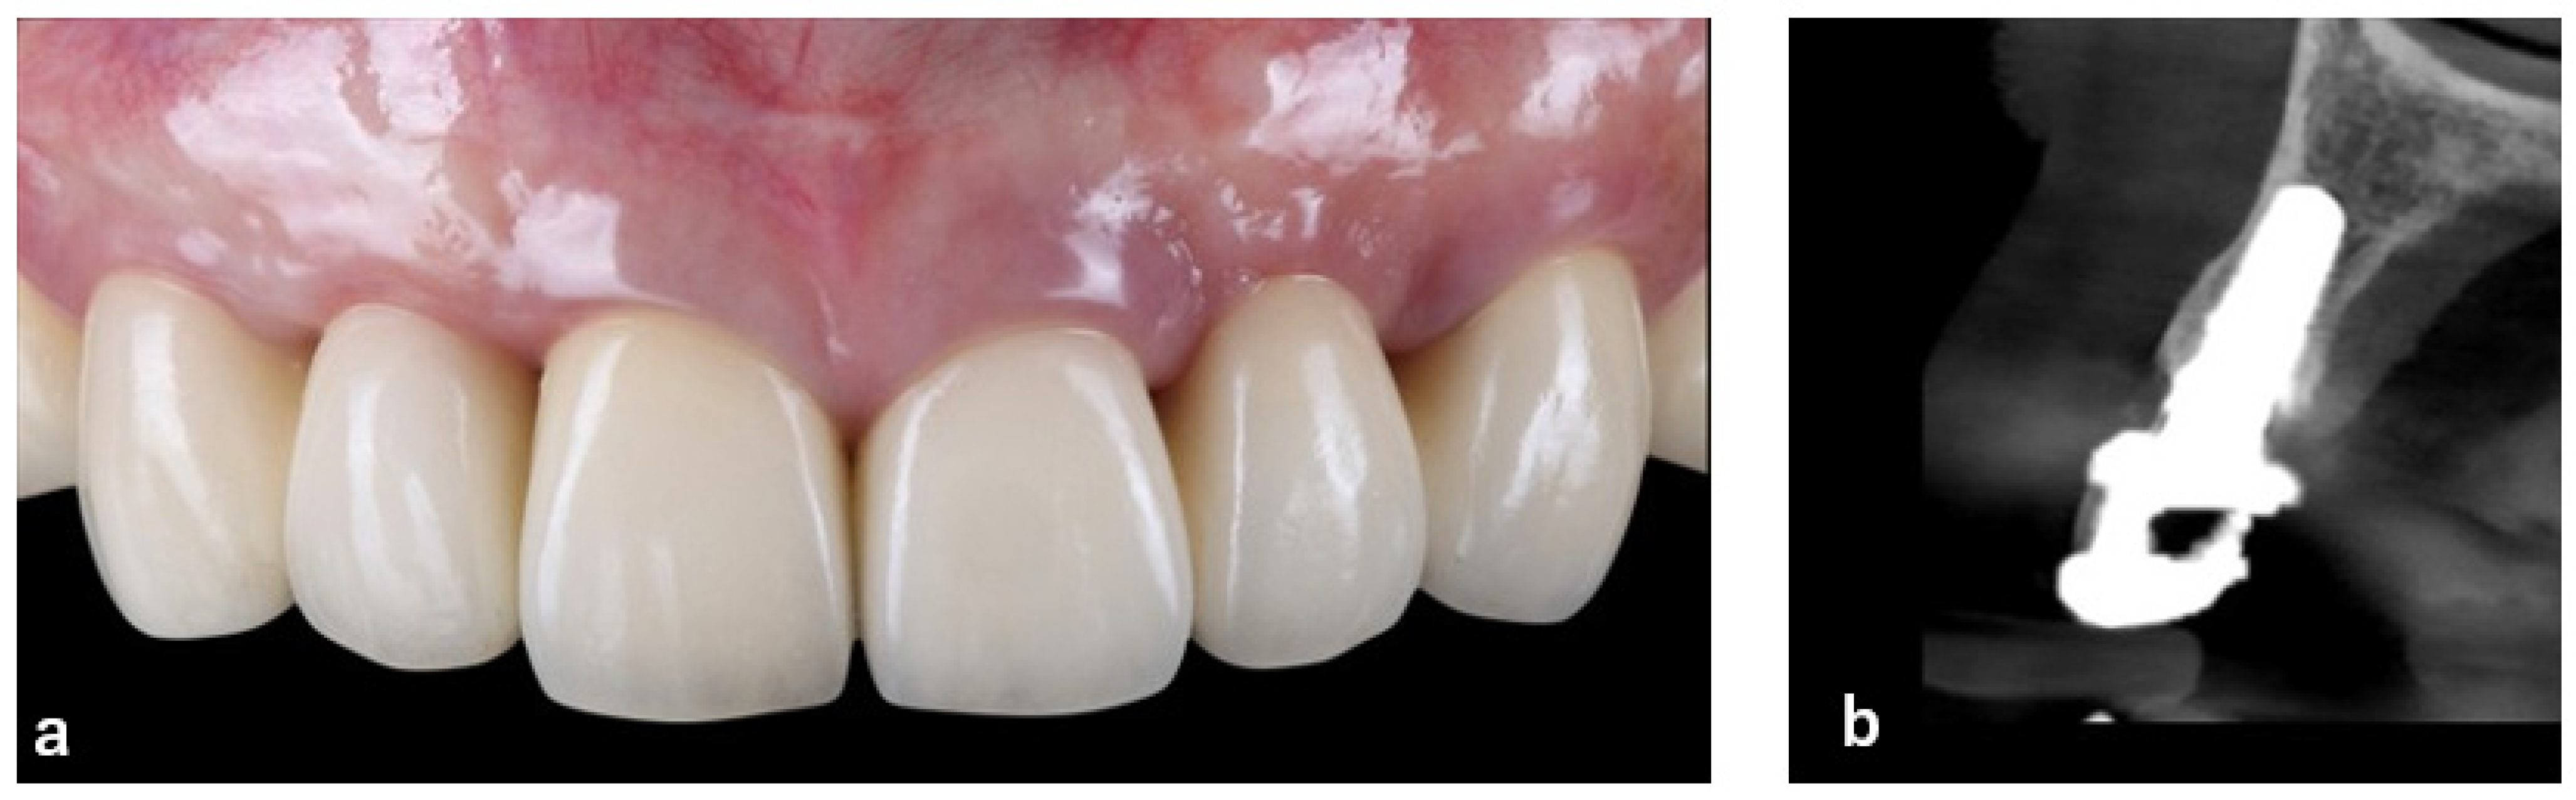

| 8 | +3 months after SGG | Final prosthetic restoration | Delivery of cantilever implant-supported prosthesis (#12–13) (Figure 11 and Figure 12) |